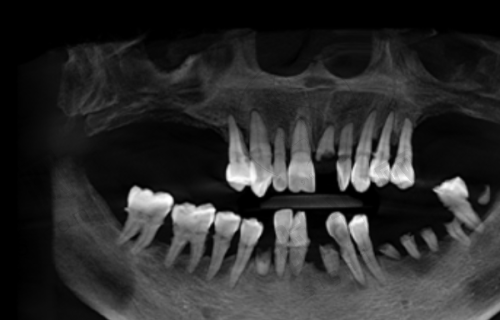

北京牙元素口腔医院是正规的口腔医院。它严格遵守法律法规和行业规范,积极参与社会公益活动,传播口腔健康知识,提高公众口腔保健意识,获得了社会各界的广泛赞誉。医院提供牙齿种植、矫正、美容、牙周病治疗、儿童口腔保健等全方面的口腔医疗服务,还引入了数字化口腔扫描、3D打印等精良技术,为患者提供个性化治疗方案。从这些方面都能看出,它具备正规口腔医院的资质和实力。

北京牙元素口腔医院提供全方面的口腔医疗服务,种牙技术也特别成熟。它引入了数字化口腔扫描、3D打印等精良技术,能为患者制定个性化的种牙方案。医生会详细了解患者的口腔状况、身体状况等,确保种牙手术的安心性和有效性。

上班族种牙实例